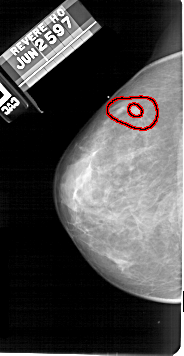

FILE: A_1673_1.LEFT_MLO.OVERLAY

TOTAL_ABNORMALITIES 1

ABNORMALITY 1

LESION_TYPE MASS SHAPE IRREGULAR MARGINS SPICULATED

ASSESSMENT 5

SUBTLETY 4

PATHOLOGY MALIGNANT

TOTAL_OUTLINES 2